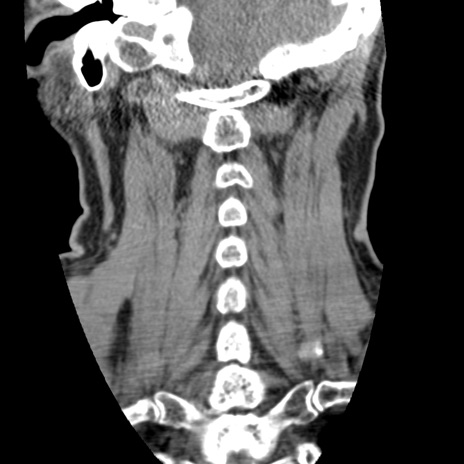

症例50 頚椎CT(冠状断像)

【症例】60歳代女性

【主訴】後頭部〜右後頸部にかけての痛み

【現病歴】本日飲食店でコーヒーを飲んでいたところ、突然後頭部〜右後頸部にかけて痛みが出現し、右上肢の感覚障害を伴ったため救急要請。

【身体所見】脳神経学的に明らかな異常所見を認めず。右上肢に軽度の感覚障害あり。

異常所見と診断は?

頚椎CT